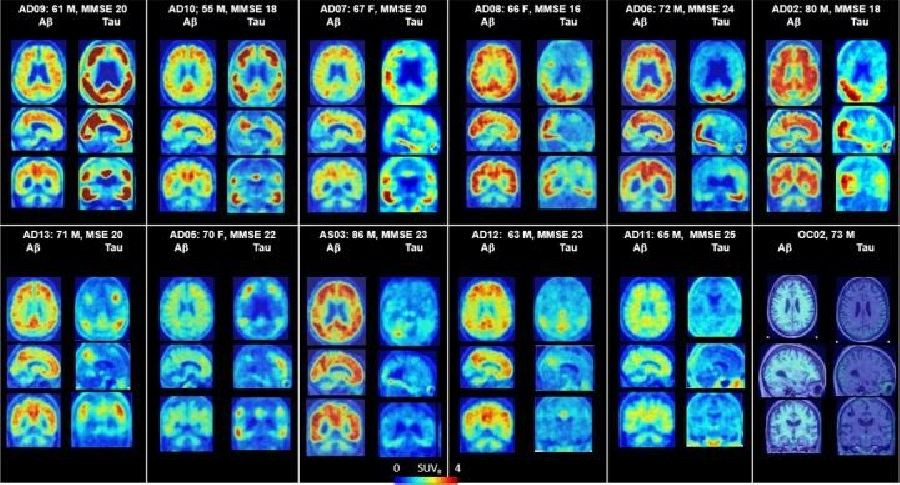

Actualmente, la captación de glucosa y el metabolismo se pueden evaluar mediante imágenes con tomografía por emisión de positrones (PET) en los hospitales. Sin embargo, los escaneos PET con trazadores radiactivos son caros y su naturaleza invasiva ha obstaculizado su aplicación clínica general. Además, los pacientes no pueden escanearse con demasiada frecuencia con trazadores radiactivos.